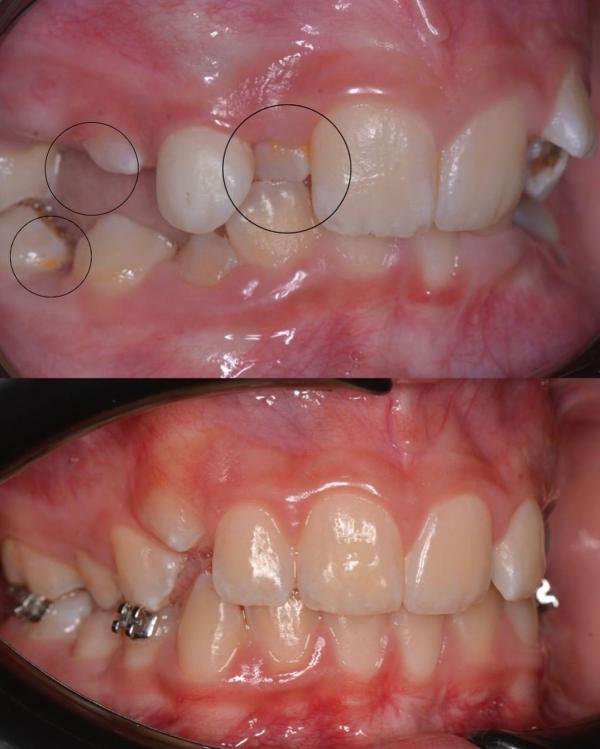

Перевоплощение длиной в 3 года …

Лечение , которое можно было бы избежать…💔

Итак , вернёмся в начало. 🖌

К этой пациентке я прониклась особенной любовью с первого визита ❤️☀️, солнечную девочку зовут Насиба, ей было на тот момент 9 лет

Пришёл ребёнок на консультацию, вижу множество проблем:

🦔Сужение верхней челюсти

🦔Дефицит места для прорезывания зубов

🦔Глубокий травматический прикус

🦔Рецесс...